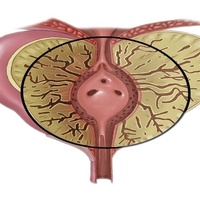

Предстательная железа относится к репродуктивной системе мужчины.

Простатит является воспалением ткани простаты. Это заболевание проявляется болями в области поясницы, промежности или таза, а также сопровождается дисфункцией нижних мочевыводящих путей.